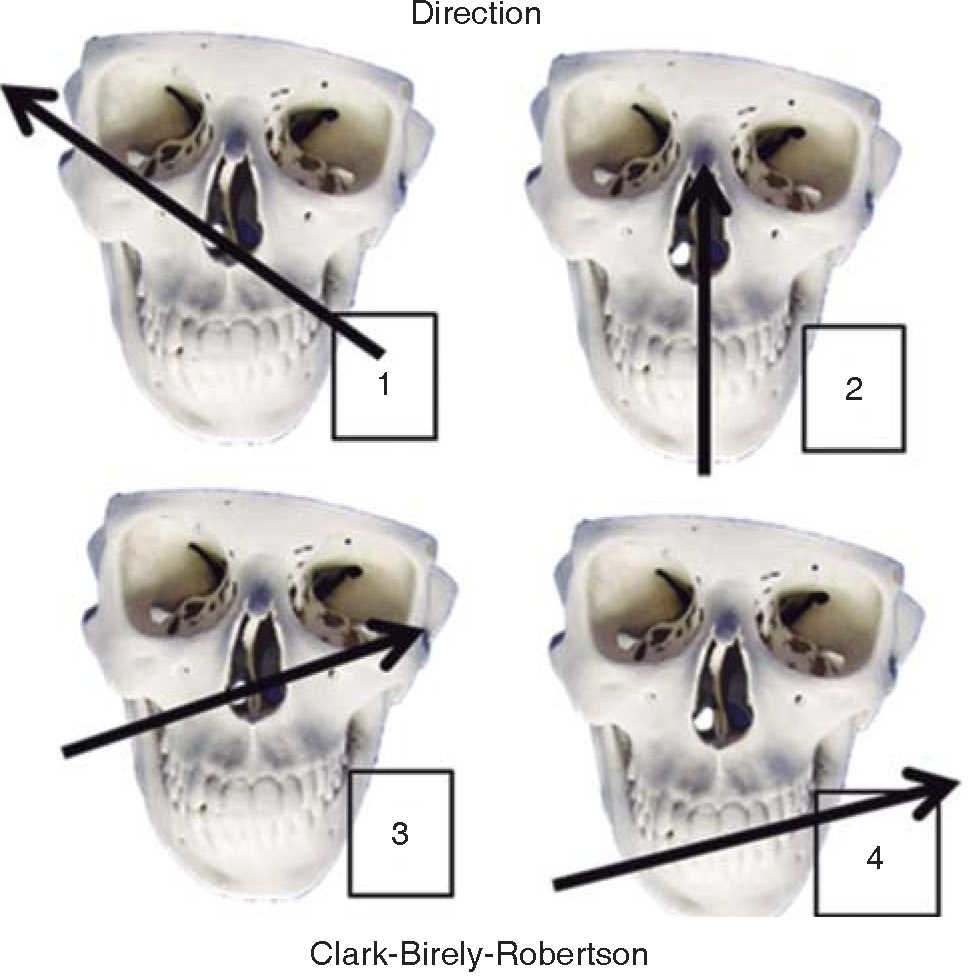

Firearms wounds are established and a guide is created to definitively treat these lesions. There are many classifications; nevertheless, we are based on four of them. The first classification is established in function of the projectile's entry and exit pattern, the second classification is established according to the weapon's caliber and distance of the projectile, the third classification, described by Clark-Birely Robertson, is in function of four possible trajectories of the projectile in the face (Figure 3),9 and the fourth classification, in low and high energy lesions, is established in function of mass loss and lesions inflicted in the face.16